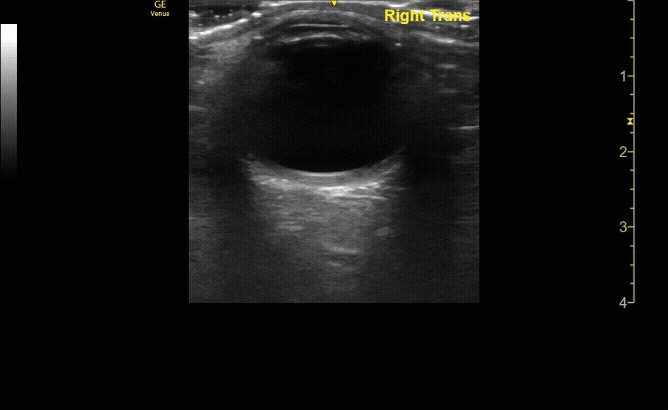

Transverse (short) view of the right eye. Ensure to scan both right and left for credit.

c/o Victoria Gonzalez, MD